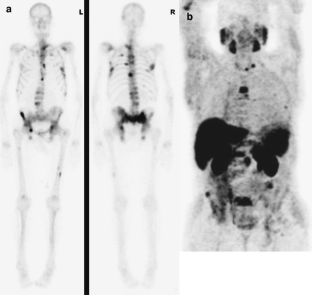

Fig. 1

Fig. 2

Fig. 3

Fig. 4

Fig. 5